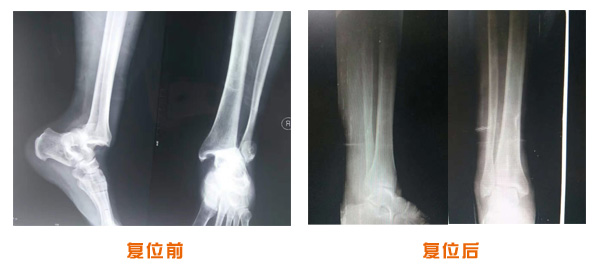

尺橈骨骨折治療前后

尺橈骨克雷氏骨折治療前后